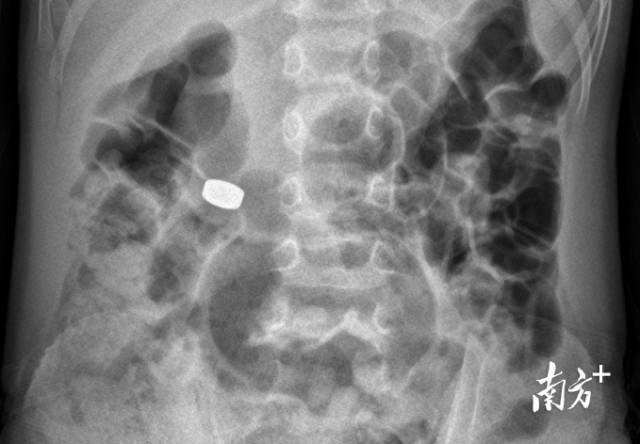

影像检查结果显示电池在胃部。

事发当晚10时,高州市潭头镇的康仔一边吃西瓜,一边在玩纽扣电池,电池“滑溜溜”触感引起了他的兴趣,便试着含在嘴里,结果不小心就吞下了肚。妈妈发现后,第一时间就带他求医。2小时后,康仔到达高州市人民医院急诊科,检查显示纽扣电池仍停留在胃内。